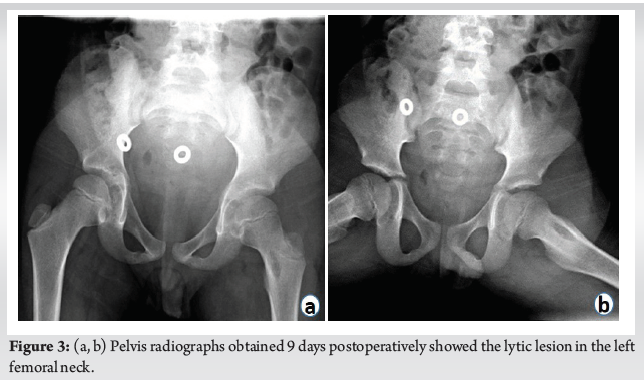

Pediatric Hip Pain with Bone Lesion, Sepsis, and Occam’s Razor = Brodie’s Abscess Case Report

Barbara Minkowitz , Jennifer Ristic , Christina Gagliardo , Eytan Mendelow , Colleen Spingarn ………………………………p.29-34